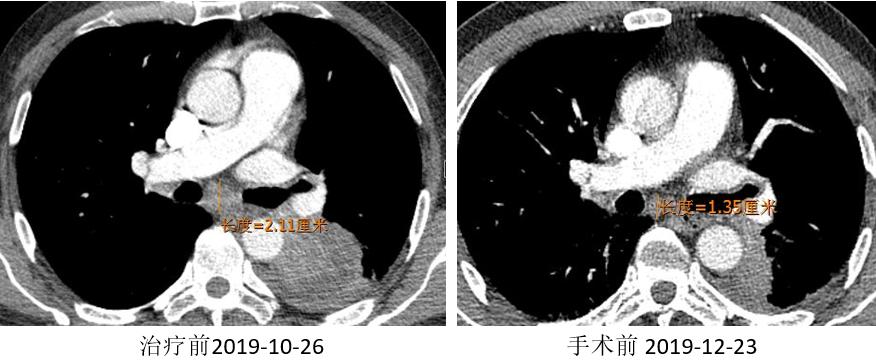

胸部CT

外周淋巴结CT

2019.12.03 行“VATS辅助切口左肺上叶袖式切除术”。

两周期“信迪利+AP”免疫治疗联合化疗方案。